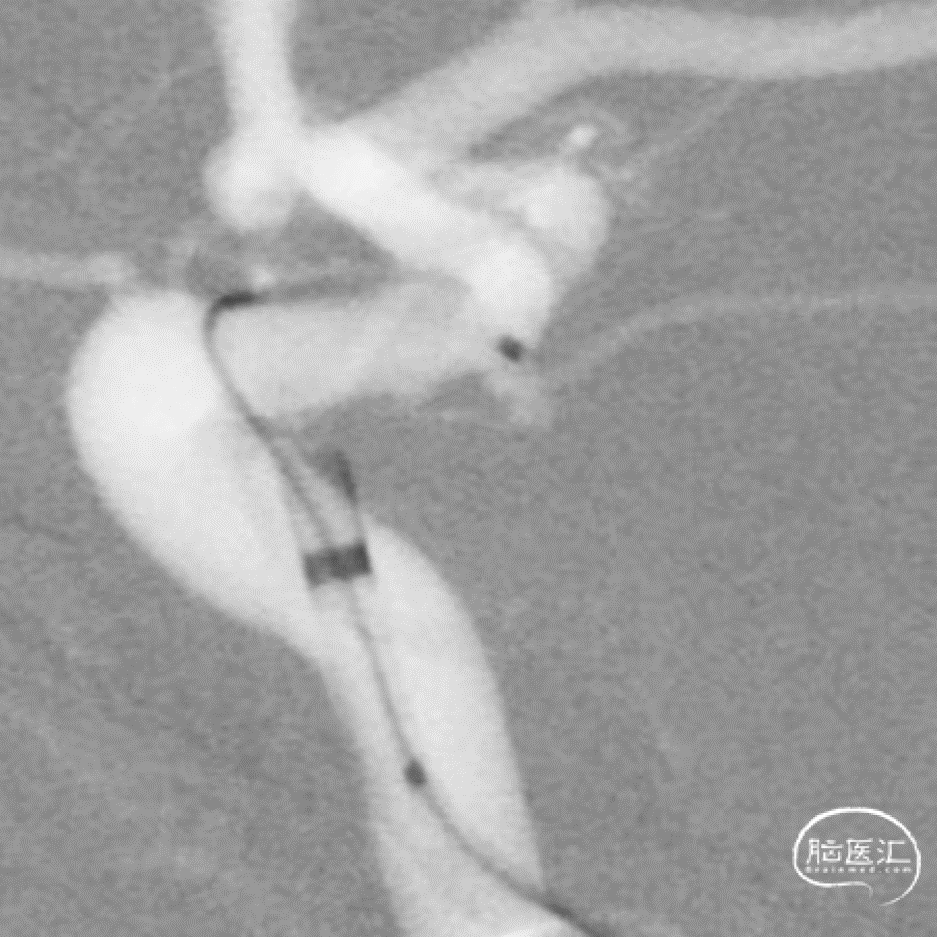

术后即刻

术后即刻支架形态

微导丝按摩

按摩后支架的形态

支架和弹簧圈重建的形态